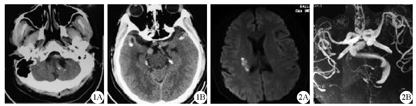

男性,24岁,因"左侧肢体麻木无力2 d"于2016年10月22日收治于日照市人民医院急诊科。患者于2 d前出现左侧肢体无力麻木,行走拖曳,左手持物不能,病情持续无缓解,无头痛头晕。既往史:既往高血压病5年,平日于家中口服降压药代文及兰迪治疗,血压控制差;1年前患者右侧动眼神经麻痹,治疗后未遗留后遗症状。入院体检:血压220/115 mmHg(1 mmHg=0.133 kPa),神志清,言语清晰,心肺腹查体未见明显异常,颅神经查体未见明显异常,左侧肢体肌力3级,右侧肢体肌力5级,肌张力正常,左侧肢体痛觉减退,双侧病理征阴性。入院诊断:脑梗死、高血压病3级。入院后血常规、血肝功能、肾功能、血脂系列、凝血系列、免疫全套检查未见明显异常。患者头颅CT、MRI+MRA检查结果见图1、图2,确诊为VBD。患者头、颈、心CT血管造影检查结果见图3。入院治疗:代文联合拜新同控制血压,阿司匹林联合波立维抗血小板治疗,依达拉奉清除脑内自由基,丁苯酞氯化钠注射液改善脑功能。住院16 d后,患者左侧肢体肌力明显改善,肌力4+级,于2016年11月7日好转出院。

CT of vertebrobasilar dolichoectasia patient

MRI and MRA of vertebrobasilar dolichoectasia patient

1A:椎动脉及基底动脉扩张、迂曲,1B:颅内血管显示多发钙化;2A:右侧基底节区梗死,双侧额顶叶白质脱髓鞘改变,左侧基底节区含铁血黄素沉积,2B:椎基底动脉及双侧颈内动脉系统血管迂曲扩张,基底动脉内径超7.5 mm,脑干、小脑受压变形